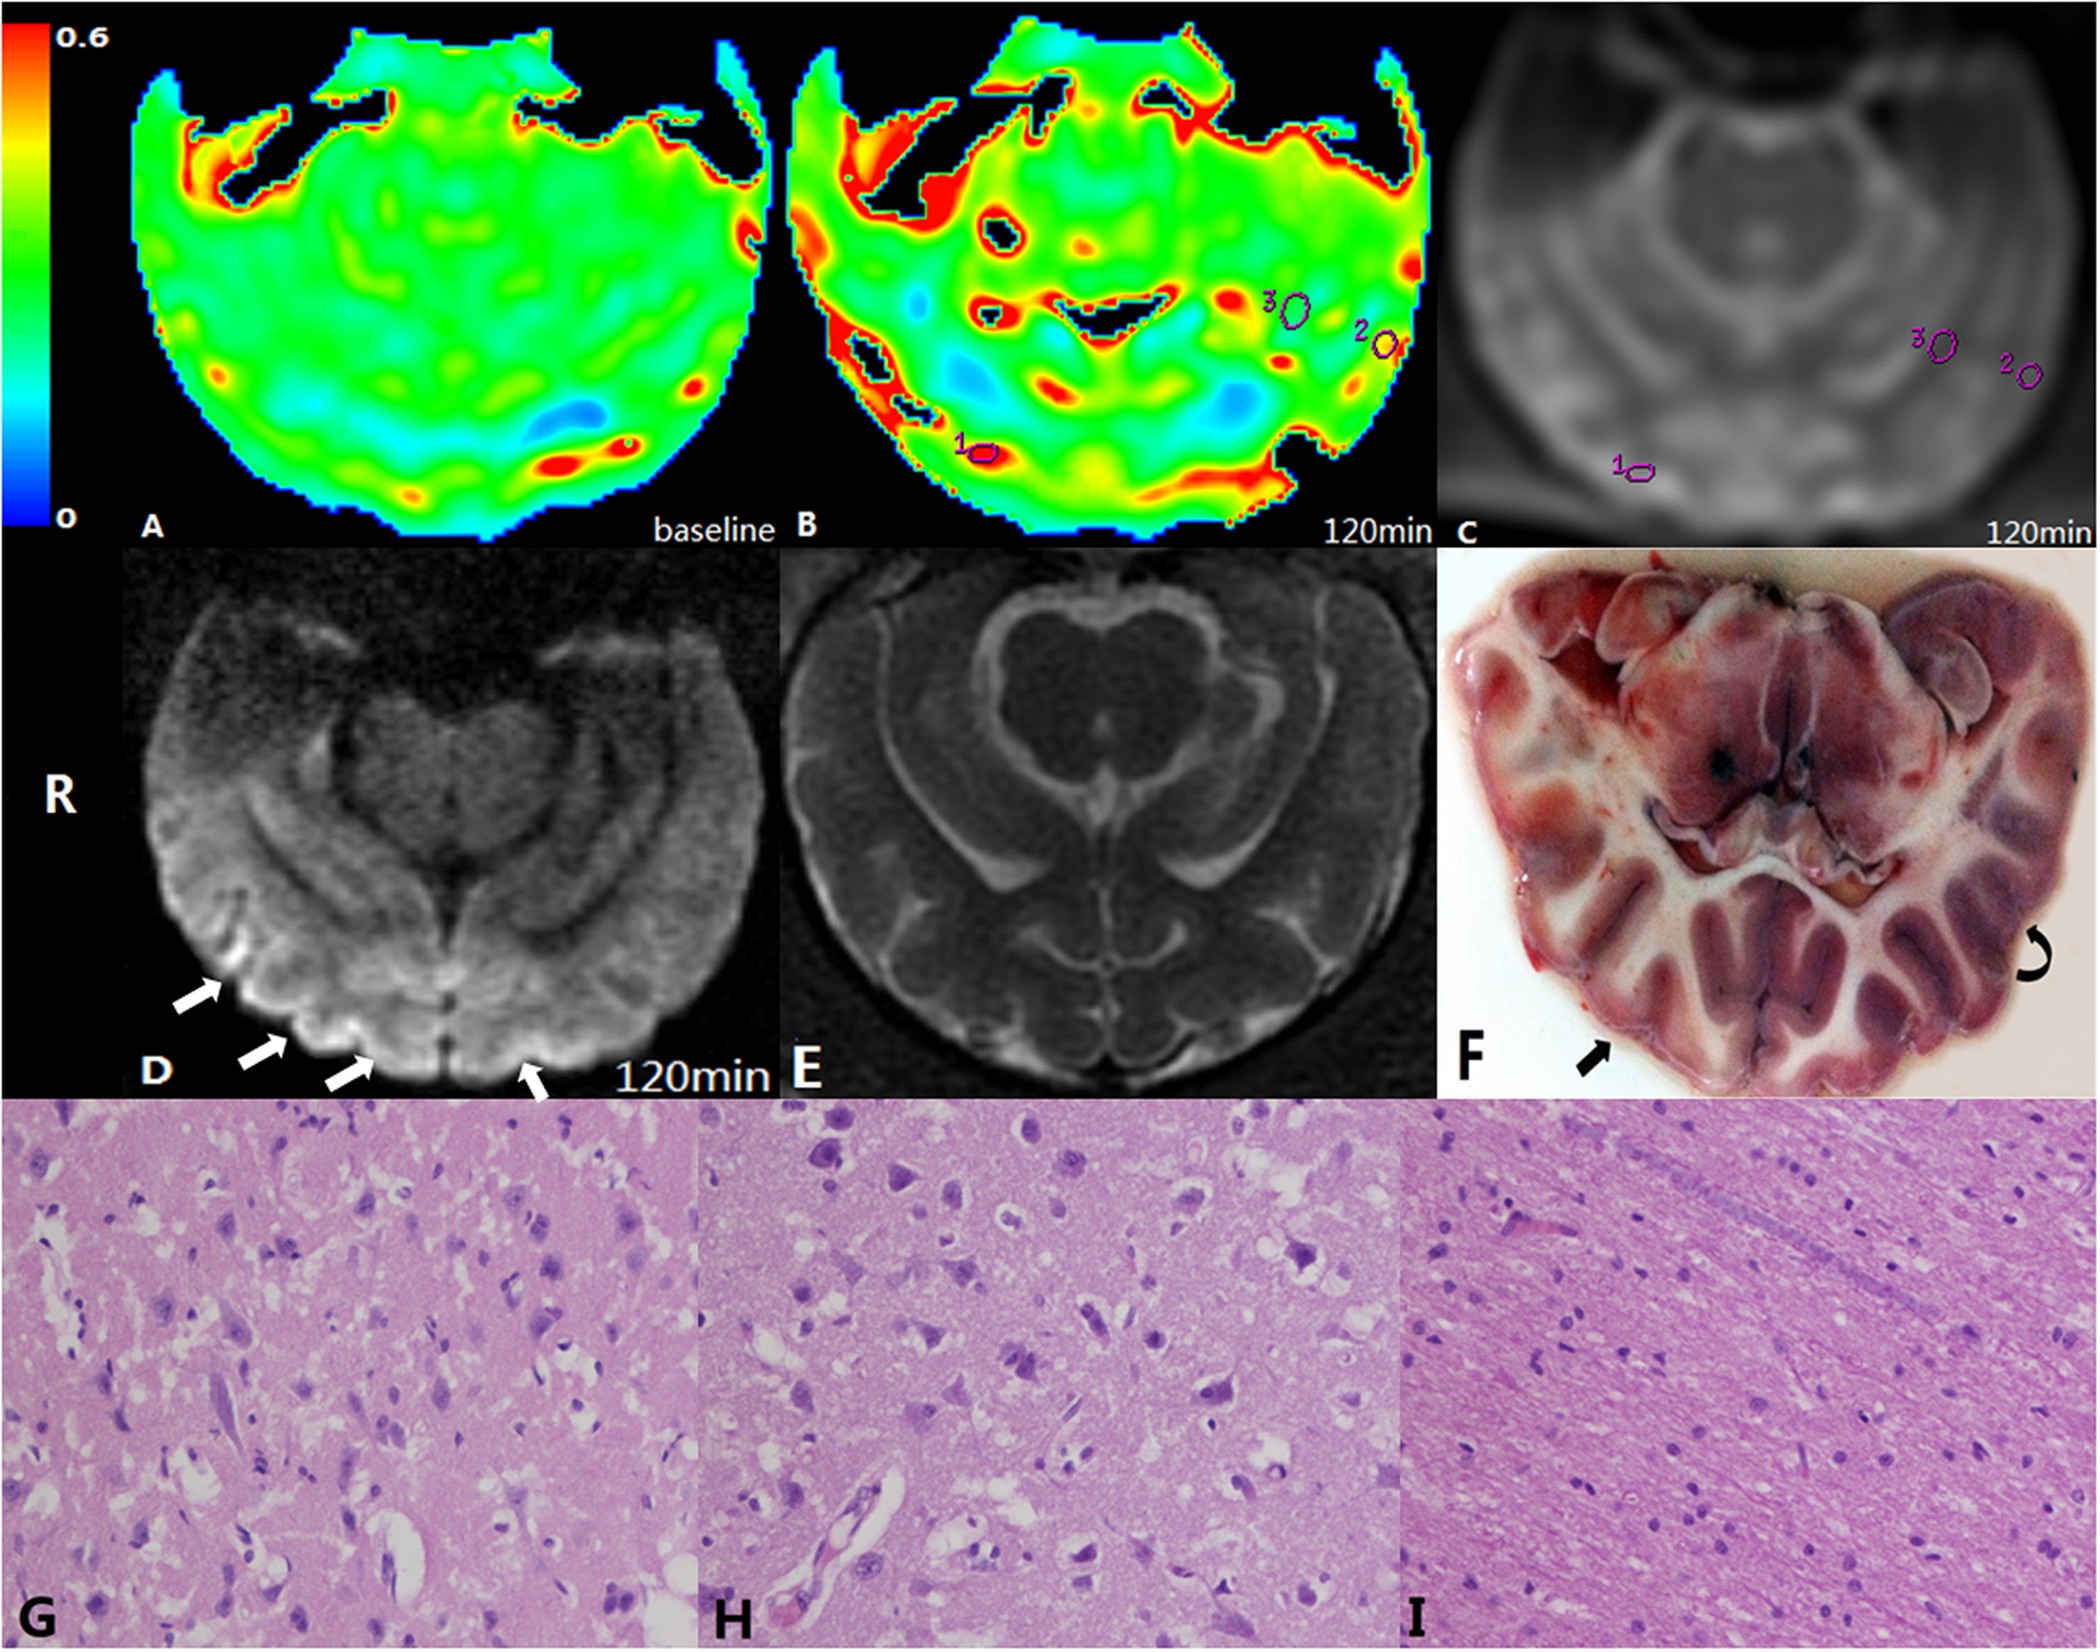

Figure 1

Illustration of ROI placement.

(A) OEF at baseline, (B) OEF map at 2 hrs after embolisation. ROIs were placed in a core (ROI 1), an ischaemic penumbra (ROI 2) and normal white matter (ROI 3). (C) Raw image of the ASE sequence, which is used to locate the ROIs. (D) DWI image at the same slice as the OEF map. The cortices of the right hemisphere and medial cortex of the left hemisphere showed a high signal (white arrow). E: T2WI image of the same slice as OEF map and DWI image. (F) TTC staining slice corresponding to the DWI image and OEF map. Infarct lesions in cortices of the right hemisphere are depicted (straight arrow) that were whitened and consistent with a high signal on DWI imaging. Some cortices in the left hemisphere were swollen but with normal colour, defined as ischaemic penumbra (curved arrow). (G–I) Microscopic views of the core (ROI 1), penumbra (ROI 2) and white matter area (ROI 3) (haematoxylin and eosin staining, ×400). Marked neuronal degeneration is shown in the core (G) whereas cell oedema is predominant in the penumbra region (H). Normal white matter depicts normal neuronal cells without nuclear karyolysis and neuronal cell loss (I).